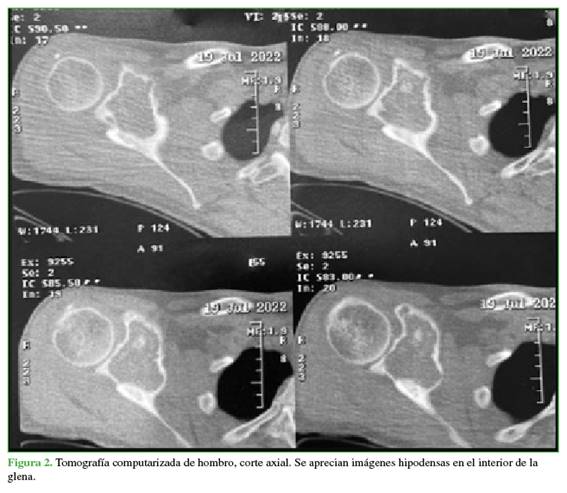

Hombre de 47 años, que consultó por omalgia derecha de un año de evolución. En el examen físico, se detectó dolor e impotencia funcional, con limitación de todos los rangos de movilidad del hombro. Se solicitaron radiografías, una tomografía computarizada (TC) y una resonancia magnética de hombro. Se visualizó una lesión tumoral lobulada, expansiva, que insuflaba corticales, con calcificaciones en su interior (Figura 1). En los cortes sagitales de la TC, se apreciaron imágenes hipodensas en el interior de la glena y, en la resonancia magnética en secuencia en T2, se observó hiperintensidad en la fosa supraespinosa que comprometía los músculos infraespinoso y subescapular (Figura 2).